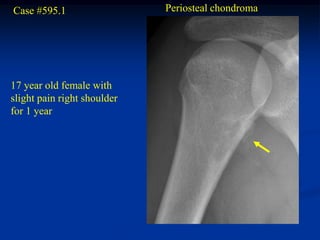

Case #595.1                  Periosteal chondroma

17 year old female with

slight pain right shoulder

for 1 year